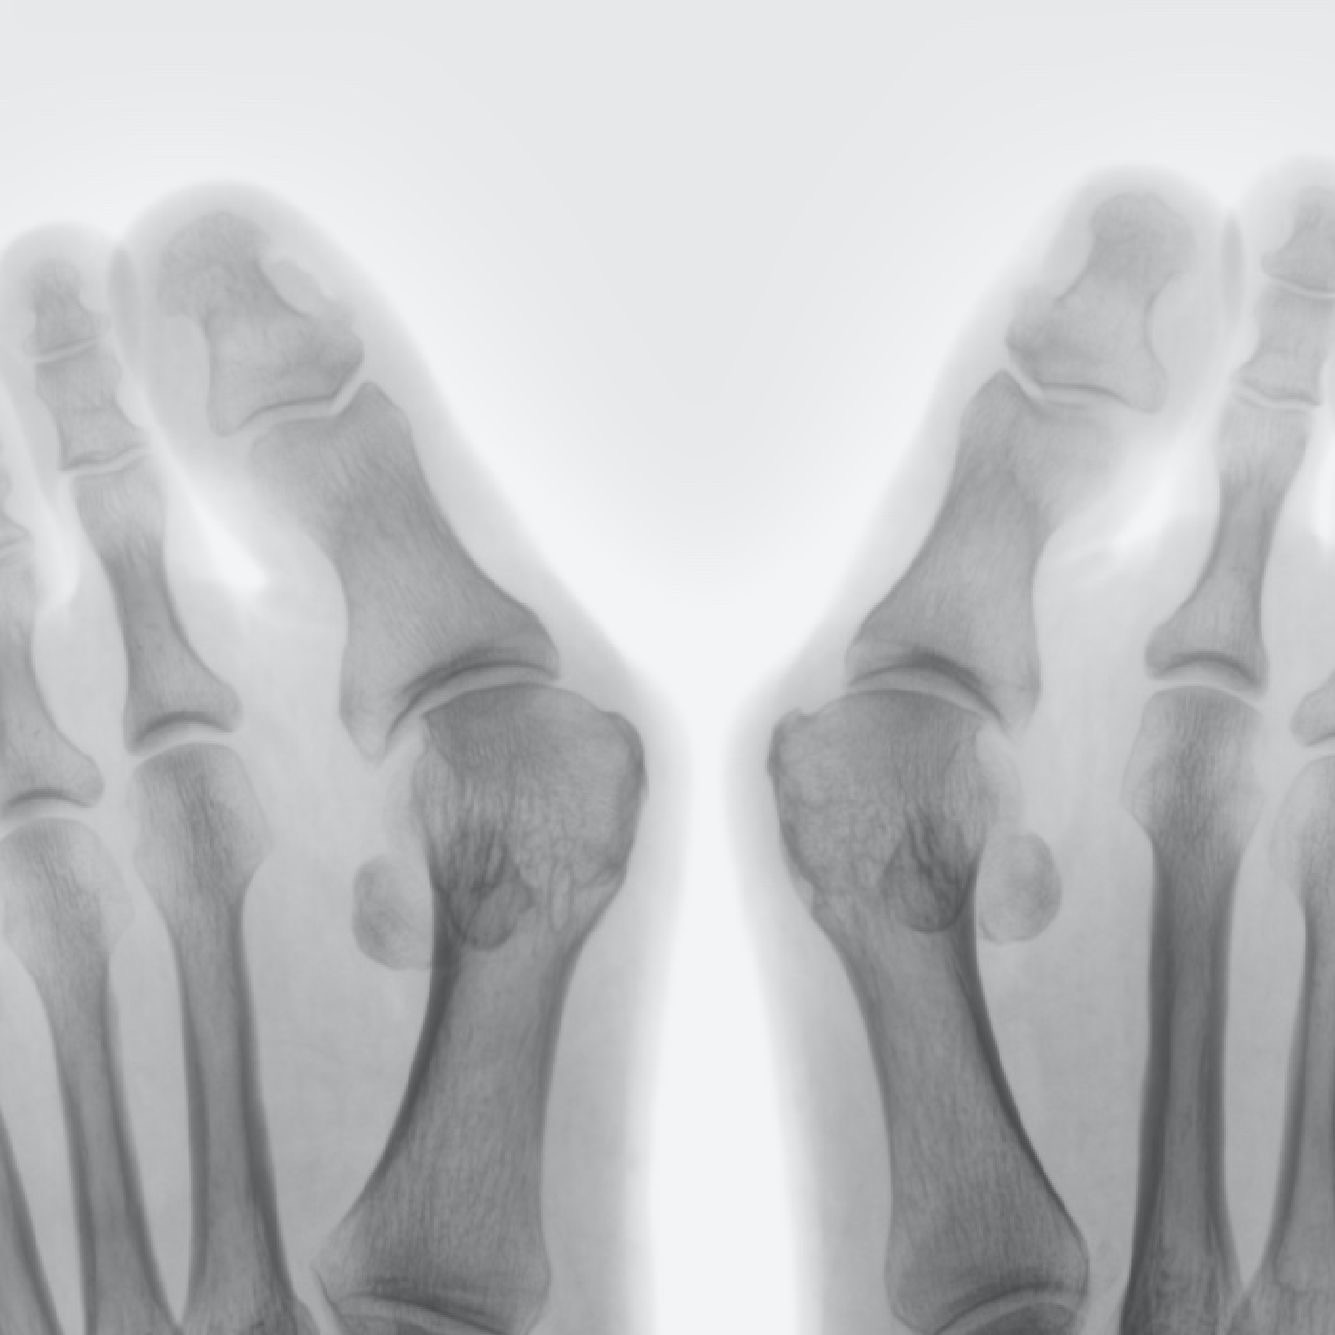

Вальгусная деформация большого пальца или Hallux Valgus является очень распространенной прогрессирующей деформацией стопы.

Халлюкс вальгус проявляется в наружнем (или вальгусном) отклонении первого пальца стопы (халлюкса) по отношению ко второму пальцу, поворотом и вращением первой плюсневой кости вокруг своего основания, что приводит к развитию болезненной костной выпуклости (или экзостоза) на внутренней стороне стопы в основании большого пальца, поэтому данное заболевание в простонародье именуют "косточка" или "шишка".

Вальгусное (наружнее) отклонение большого пальца (халлюкса) по направлению к другим пальцам стопы является одним из основных "видимых" симптомов заболевания, наряду с появлением костного выступа, известного как "косточка" или "шишка" на внутренней стороне основания большого пальца стопы.

Золотым стандартом исследования при планировании хирургического лечения является рентгенография стопы в прямой и боковой проекциях с нагрузкой.

Угол отклонения большого пальца стопы более 15 градусов является диагностическим критерием патологического вальгусного отклонения. Так же в качестве дополнительных диагностических методов возможно применять МРТ, КТ, плантографию, биомеханический анализ походки и давления.